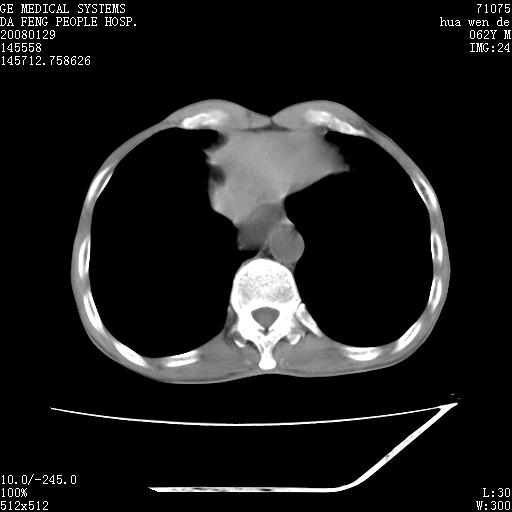

男性,67岁。作肺部检查时发现

右肺脓肿 胸腔胃

考虑:胸腔胃并支气管瘘(并发肺炎,肺脓肿形成)。

理由:1、右上肺内病灶,空洞形成,有液平。

2、肺内多处炎症。

3、前段肺内炎症,支气管引流通畅,与肿块无关系。

考虑:胸腔胃并支气管瘘(并发吸入肺炎,肺脓肿形成)。

1.整个食管扩张,未见明显占位性病变,贲门区亦未见明显占位病变,考虑:贲门失驰缓症;

2.右上肺病变边缘可见毛刺,囊壁厚度不均匀,周围境界较清楚,未见炎性渗出性影,右上肺外带可见片状影,边缘不清,考虑:肺癌伴空洞形成、右上肺炎。

食管全程扩张,壁均匀不厚,喷门失弛缓症

右上肺空洞可见液平,临近肺野磨玻璃密度,考虑1.结核2.脓肿